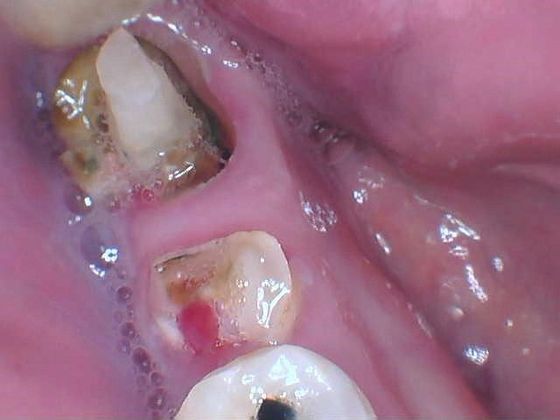

Patient had severely decayed and broken teeth replaced by dental implants